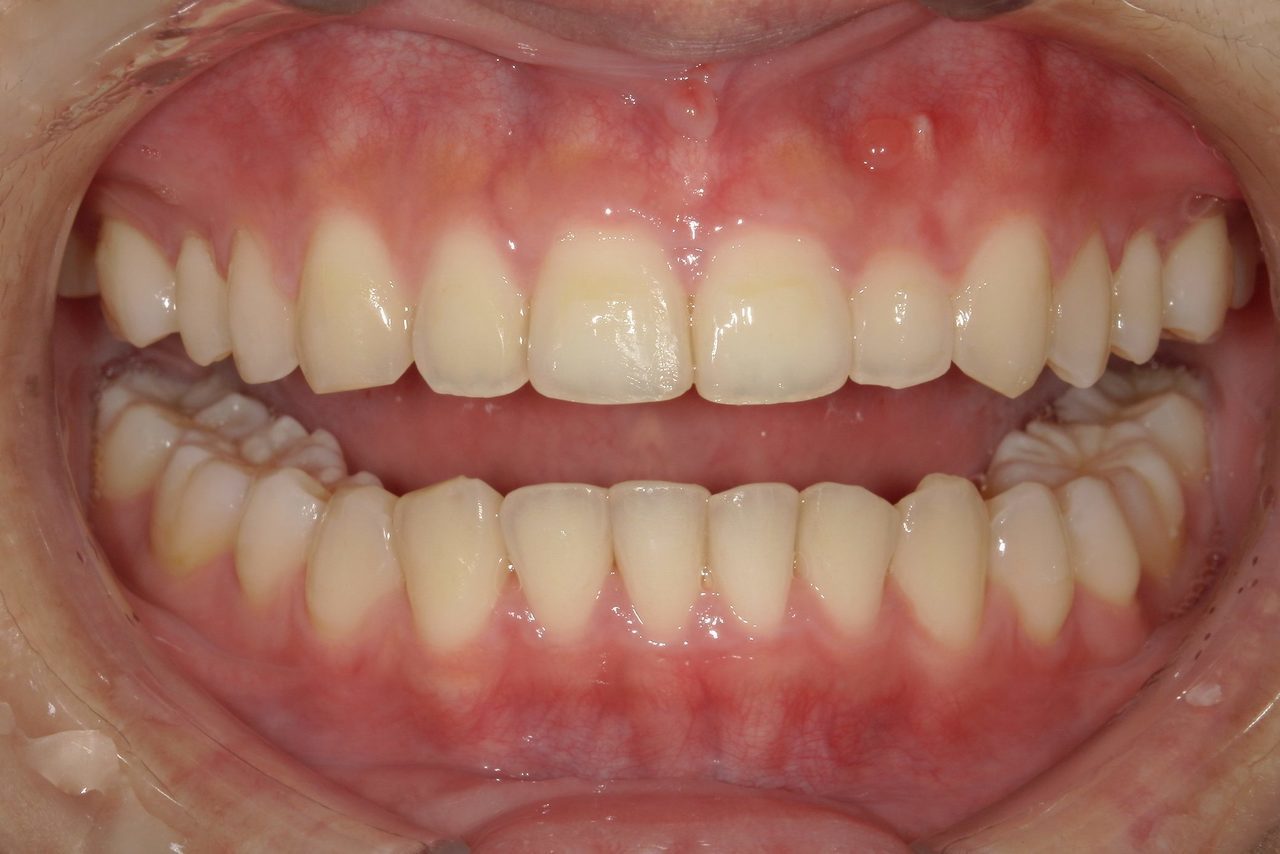

After

浜松市中央区・自動車学校前駅のインビザラインの症例

N.T 20代女性

上の前歯が出ているのが気になる、左下の第二小臼歯が内側に入っているのが気になるとの主訴でご来院。

上の前歯を下げて左下の第二小臼歯を外に移動させることで気になっていた上顎前突を改善しました。

治療の期間:R4. 4/22〜R6. 11/2

治療の価格:66万円